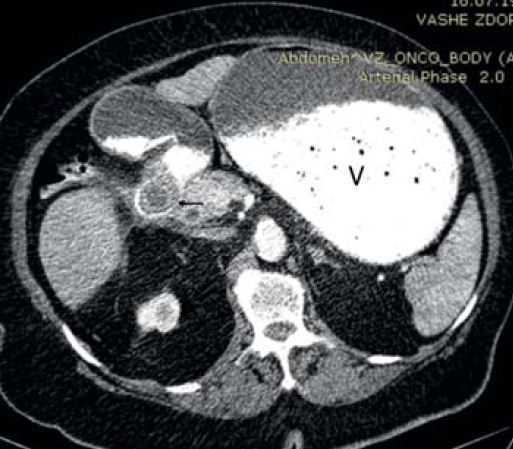

Пациентка, 76 лет, поступила в клинику с жалобами на рвоту съеденной накануне пищей, тяжесть, вздутие в верхних отделах живота, потерю веса, слабость. Из анамнеза – болеет около 3 недель, ранее неоднократно отмечала приступы боли в правом подреберье. При поступлении отмечались вздутие верхних отделов живота, наличие шума «плеска», признаки обезвоживания – сухость и дряблость кожных покровов, явления олигурии. Больная обследована. По данным КТ области брюшной полости в нисходящей ветви двенадцатиперстной кишки определяется слоистый конкремент размерами до 31×25 мм. Стенки нисходящего отдела двенадцатиперстной кишки утолщены, наружный контур нечеткий. Окружающая жировая клетчатка инфильтрирована, в т.ч. между головкой поджелудочной железы и кишкой. Желудок значительно растянут содержимым (рис. 5, 6). Лабораторно обращали на себя внимание явления гиперкоагуляции наряду с повышением уровня эритроцитов и гемоглобина (178×1012/л и 5,86 г/л соответственно), дисэлектролитными расстройствами.

Рис. 5. Компьютерная томограмма, аксиальная проекция: билиарный конкремент (стрелка), обтурирующий просвет двенадцатиперстной кишки в нисходящей части; аэробилия; желудок, растянутый содержимым (V)

Рис. 6. Компьютерная томограмма, фронтальная проекция: выраженное расширение желудка (V) на фоне обтурации двенадцатиперстной кишки конкрементом